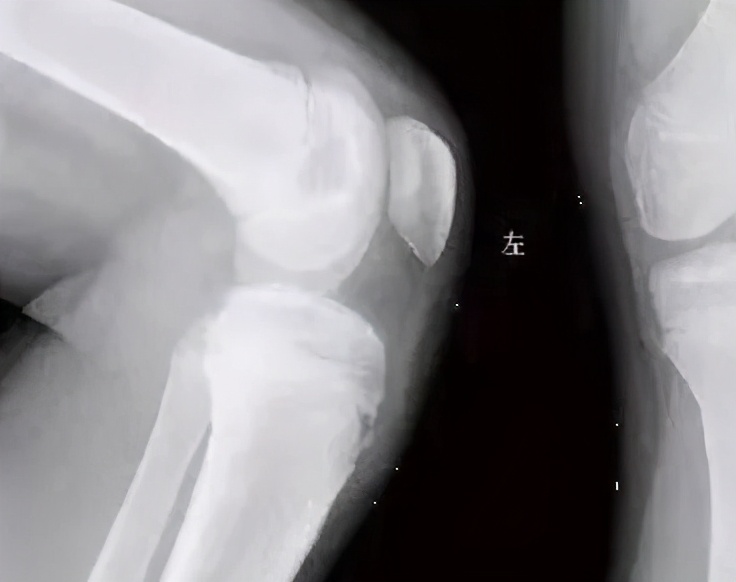

门诊一男性患者,在跑步后突然感觉疼痛,之后在做跳跃、用力伸膝动作时疼痛加剧,疼痛严重时甚至出现跛行,查体在做股四头肌抗阻力伸膝时,压痛明显加重,关节腔无积液,X线检查胫骨结节骨骺有突起表现,严重时局部肿胀,偶有发红,皮温高。医生诊断为胫骨结节骨软骨炎,建议其保守治疗,先控制疼痛,然后进行康复锻炼。

局部软组织肿胀为重要的基本征象,尤其以髌韧带的增大或增厚最为显著,以后肌腱可产生继发性钙化或骨化。

胫骨结节骨骺不规则增大,密度不匀,有节裂或边缘光滑的游离骨块。